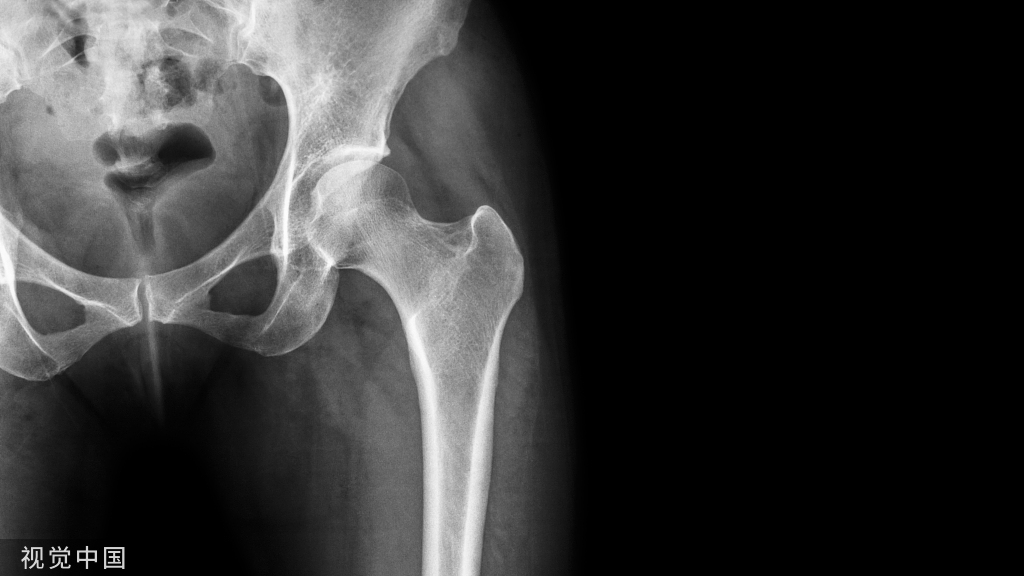

图a、 b  X线侧位和前后位影像显示腰椎序列完整,L2~ L5明显骨质增生,L5后缘骨质破坏。